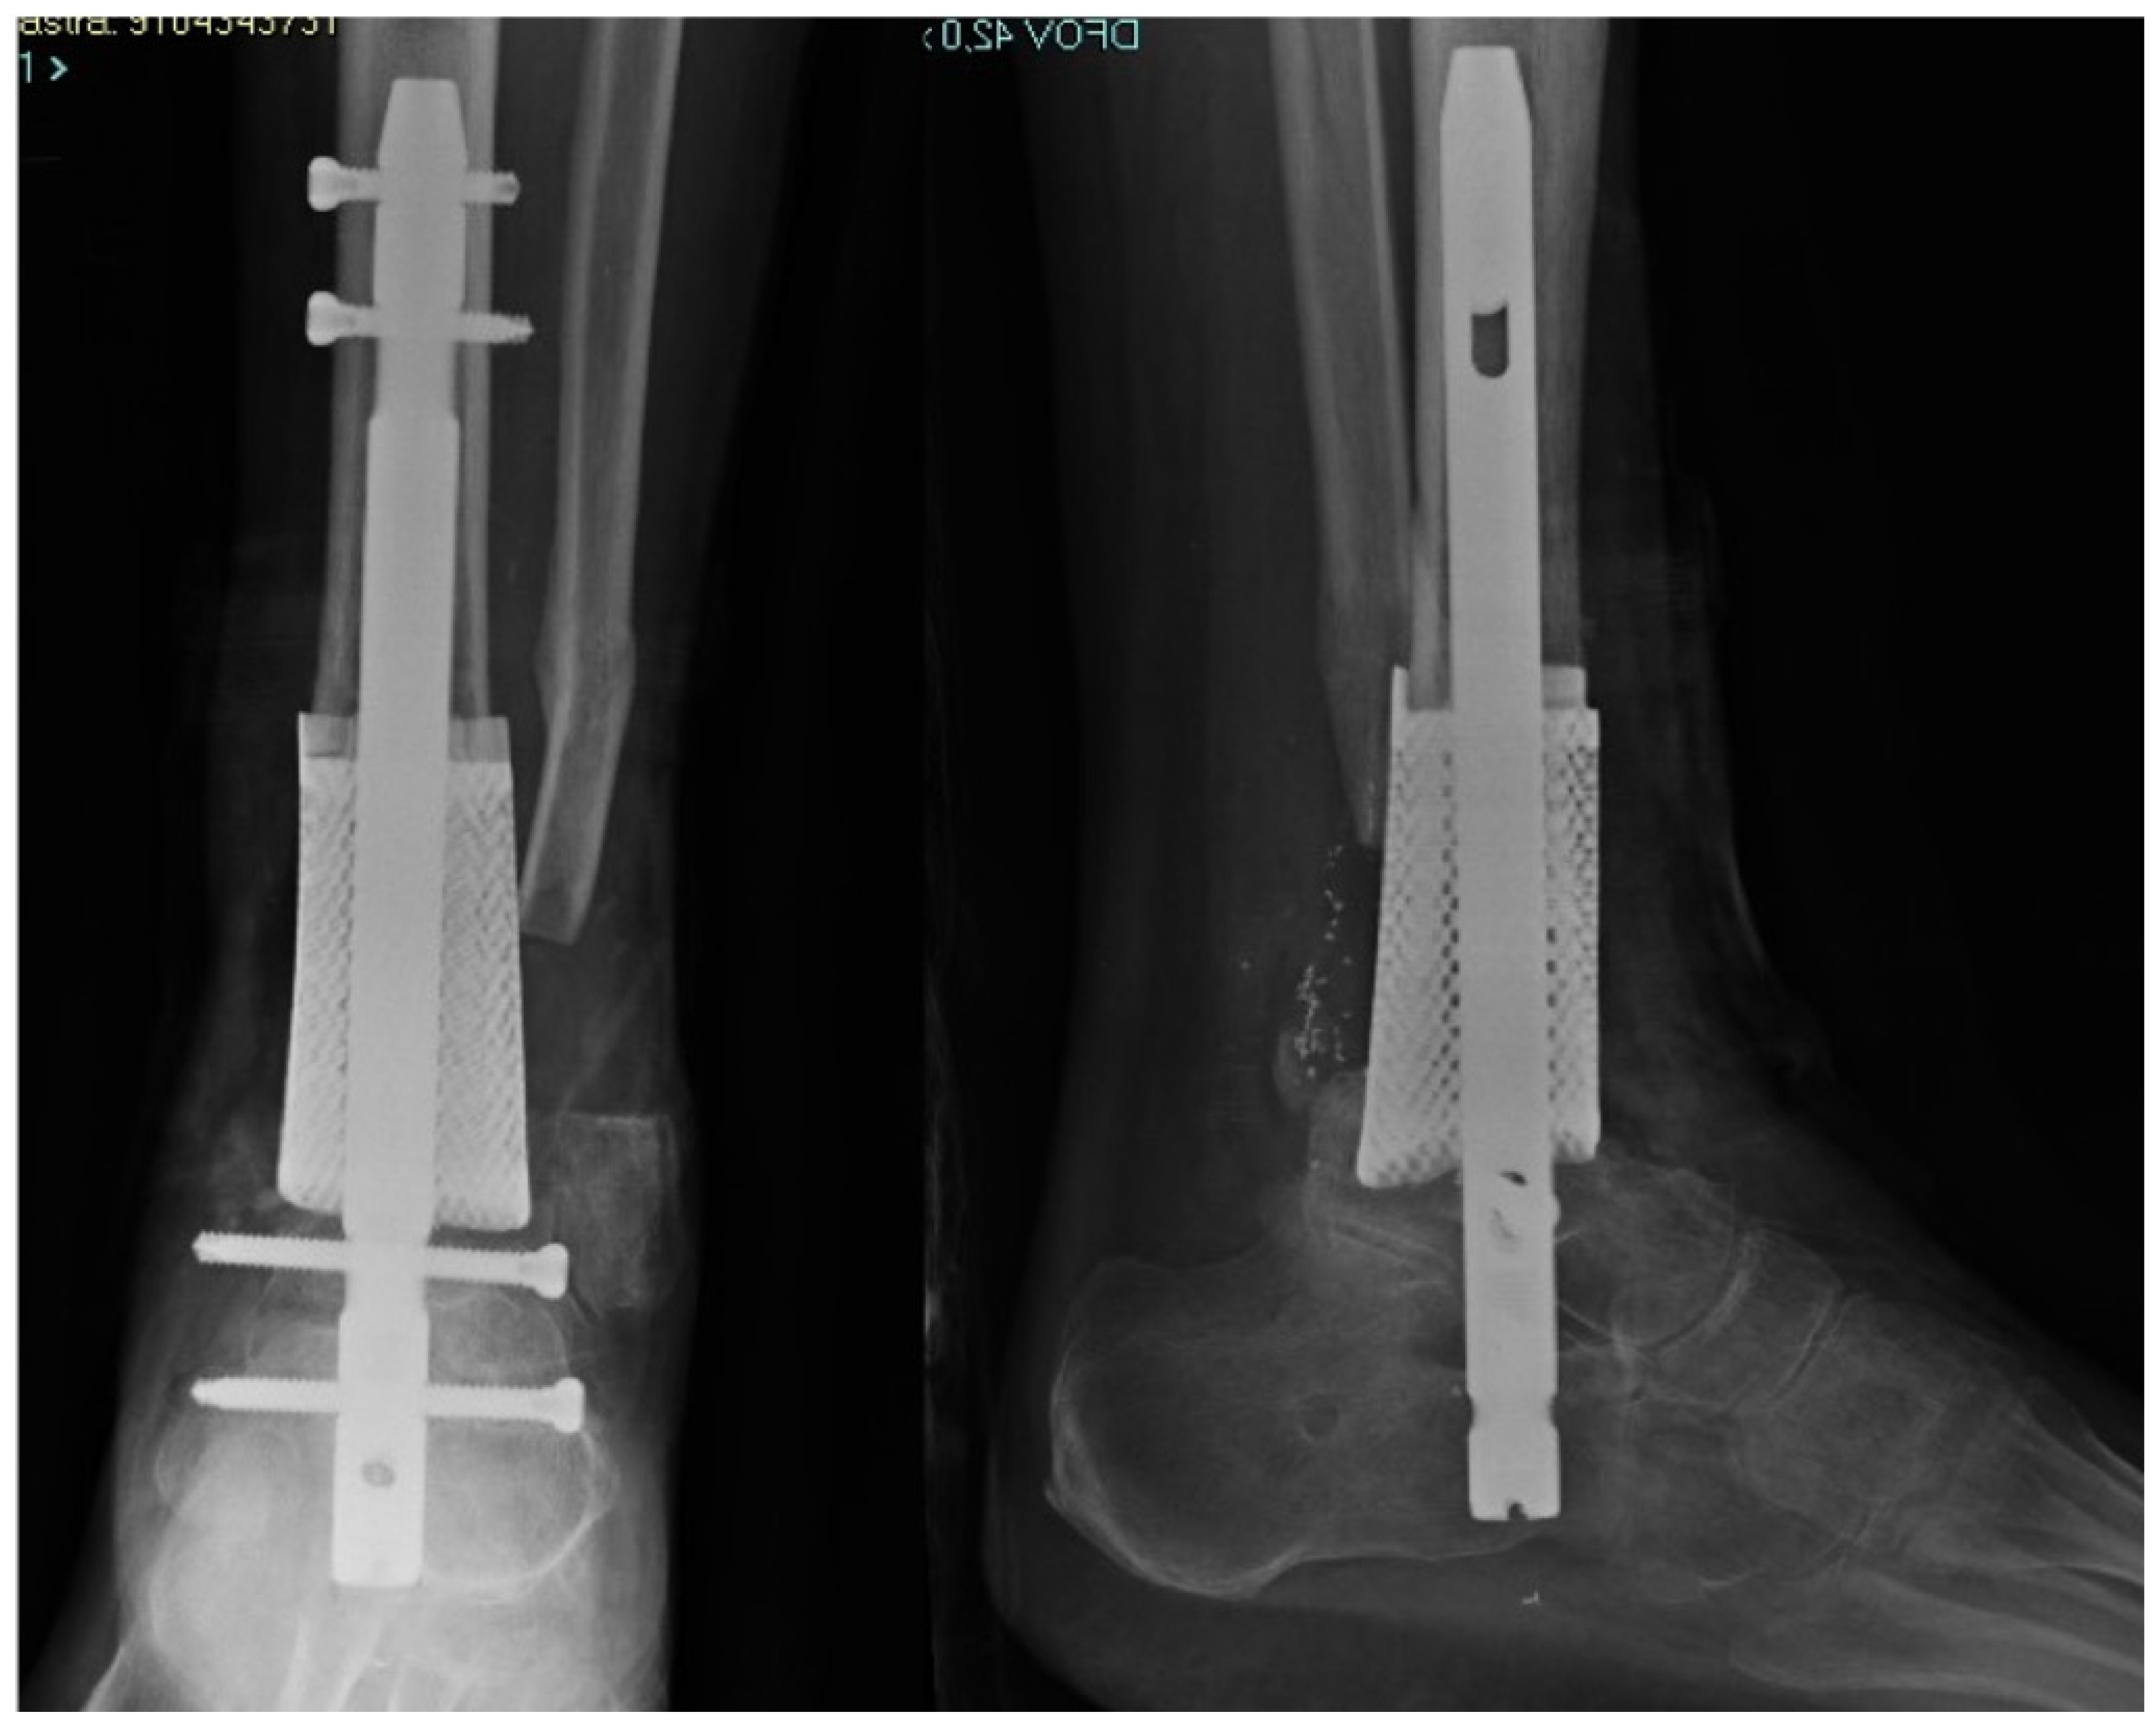

Custom-Made Implants in Ankle Bone Loss: A Retrospective Assessment of Reconstruction/Arthrodesis in Sequelae of Septic Non-Union of the Tibial Pilon

2. Materials and Methods

2.1. Planning Procedures and 3D Technology

2.2. Study Population

3. Results